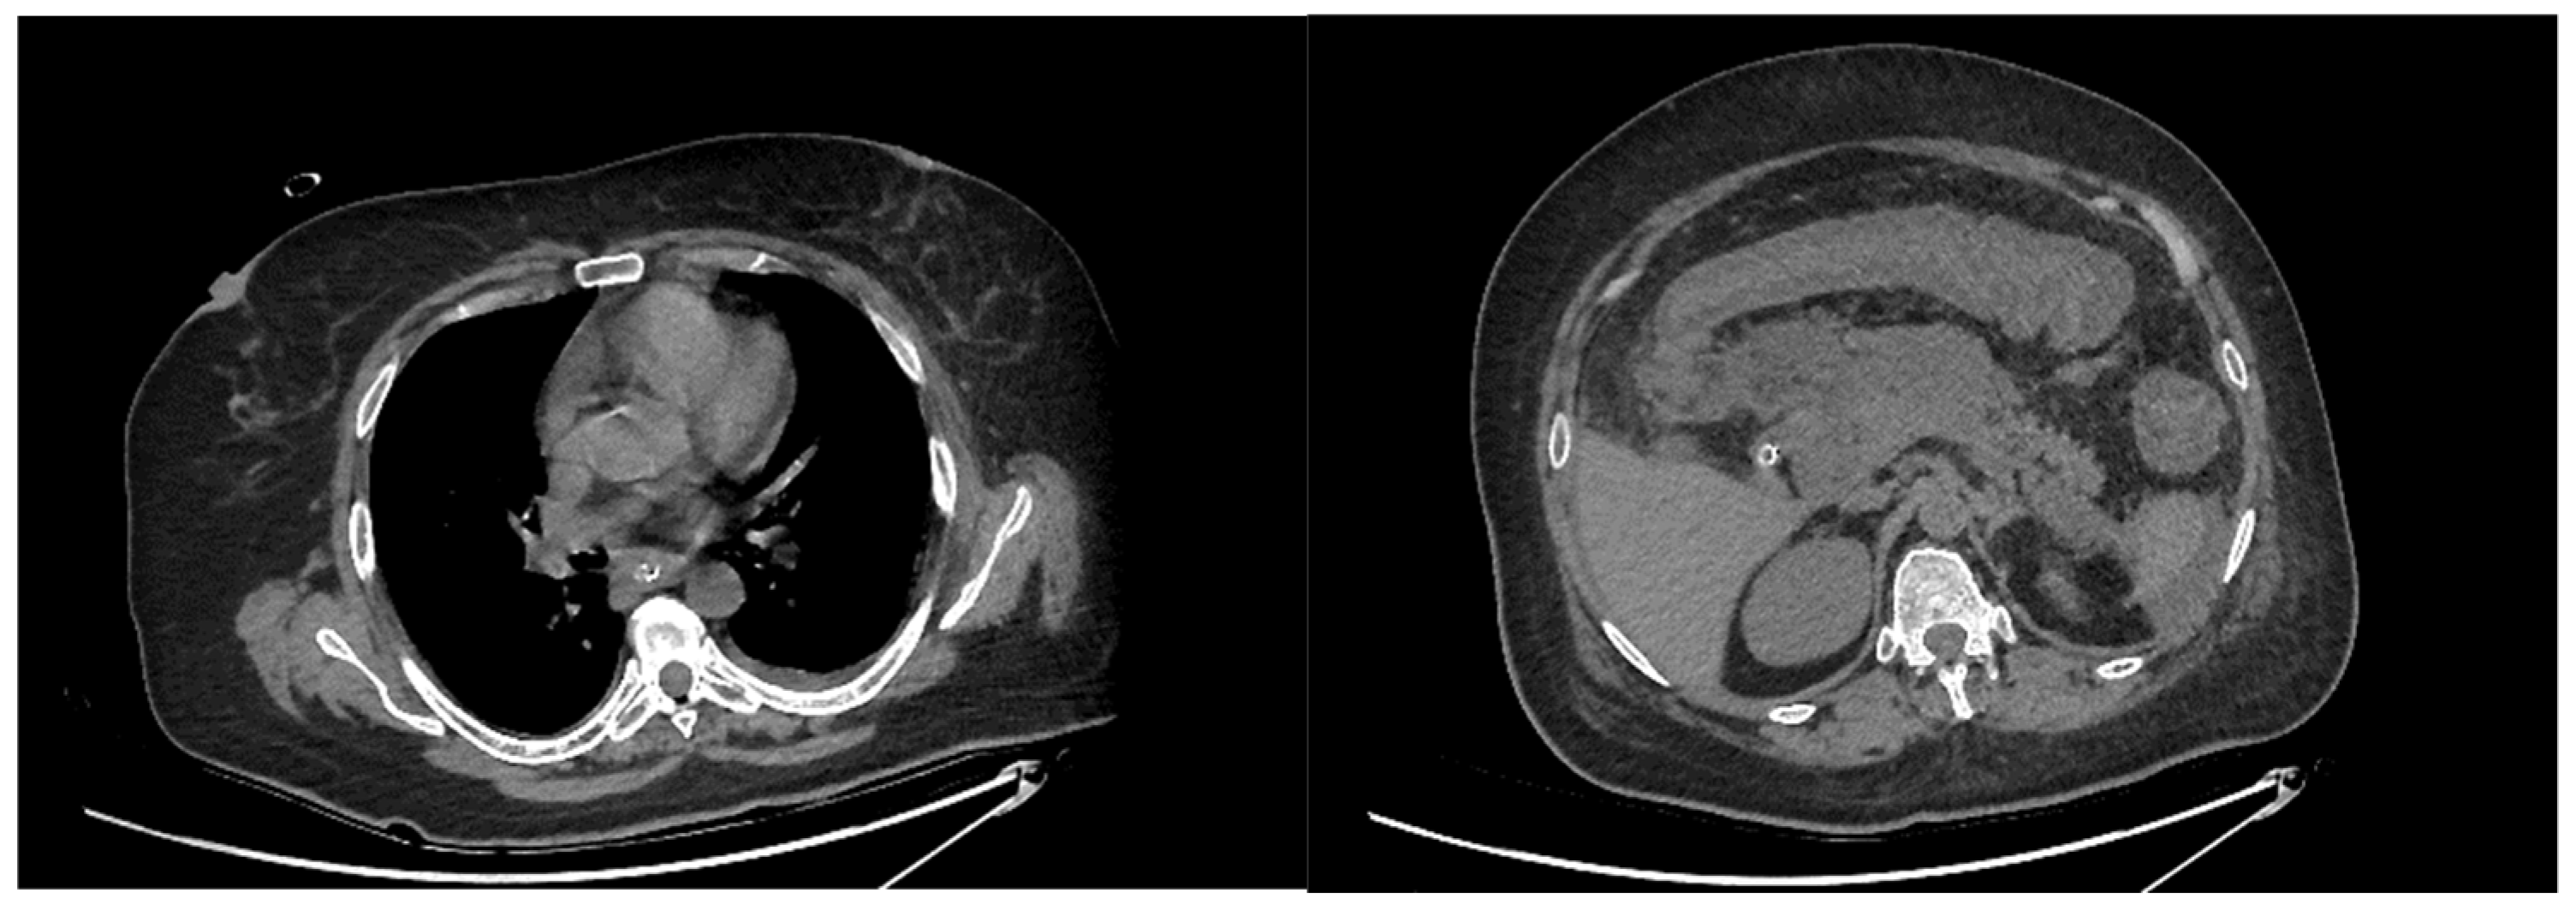

Acute Esophageal Necrosis in Acute Pancreatitis—Report of a Case and Endoscopic and Clinical Perspective

Grigore, M.; Enache, I.; Chirvase, M.; Popescu, A.L.; Ionita-Radu, F.; Jinga, M.; Bucurica, S. Acute Esophageal Necrosis in Acute Pancreatitis—Report of a Case and Endoscopic and Clinical Perspective. Diagnostics 2023, 13, 562. https://doi.org/10.3390/diagnostics13030562